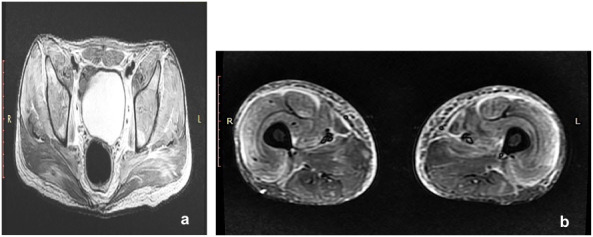

Result: A 17-year-old male presented with subacute marked diminution of vision along with arthralgia, weakness of all four limbs and development of multiple rashes around body. Fundus examination revealed bilateral multiple Purtscher flecken, pseudo-cherry red spot, and intra-retinal haemorrhages with cotton wool spots. Systemic and laboratory examinations, magnetic resonance imaging (MRI) and biopsy of tissue confirmed the diagnosis of juvenile dermatomyositis with PLR.